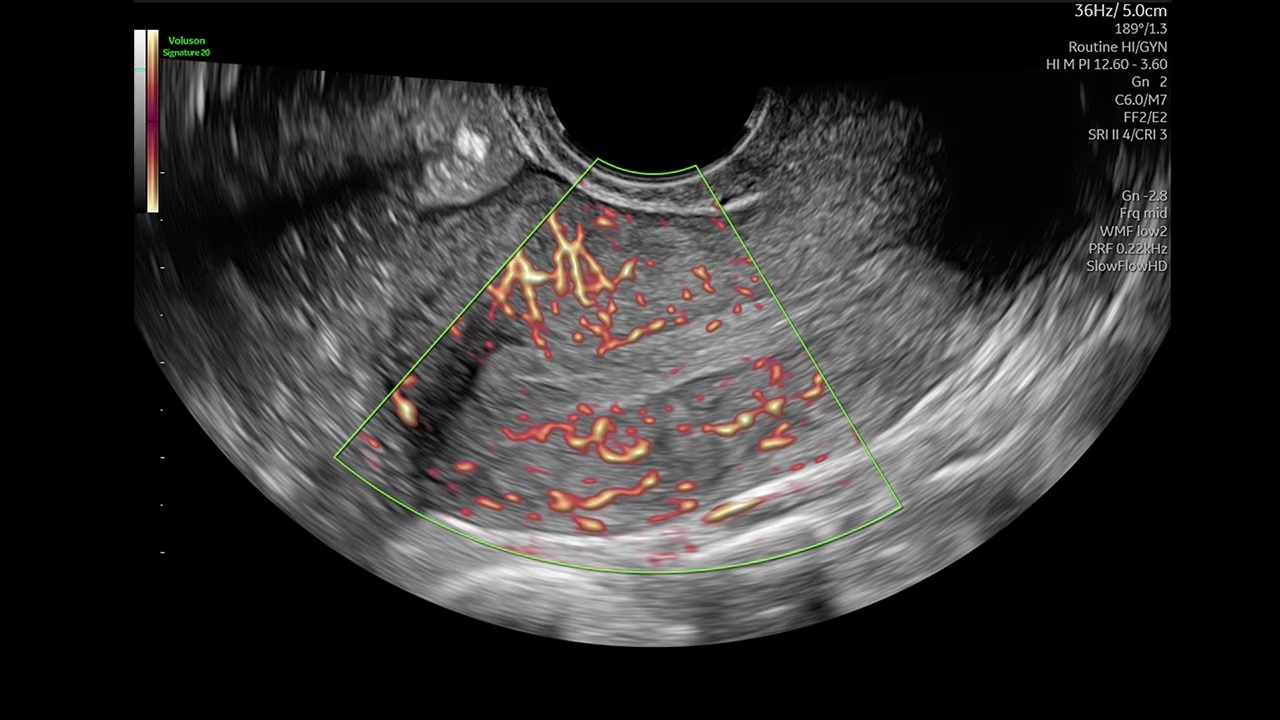

Expand the range of visible blood flow to visualize blood perfusion in very small, low velocity vessels.